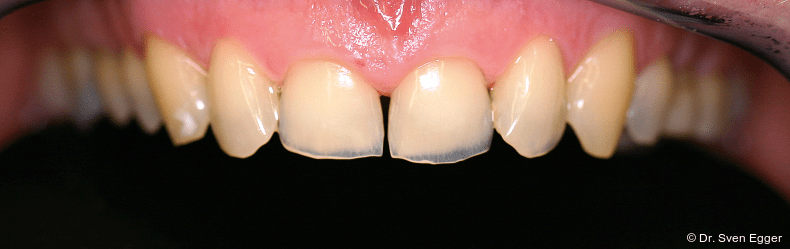

Bei der zahnmedizinischen Anamnese stellte sich ein hoher Konsum säurehaltiger Getränke (v. a. Coca-Cola light) heraus, welcher zu generalisierten Erosionen im Gebiss geführt hat. Die Zähne 36 und 47 wurden aufgrund endodontischer Vorbehandlung/Kronenfrakturen vor ca. vier Jahren entfernt. Der Leidensdruck, insbesondere verursacht durch die immer kürzer werdenden Frontzähne, bewog sie nach Aufklärung/Beratung zu einer Gesamtrestauration in allen vier Quadranten mit Presskeramikteilkronen und -veneers sowie drei Einzelzahnimplantaten.

- Parafunktion mit massivem Zahnhartsubstanzverlust(Erosionen/Abrasionen) bei bestehender Deckbisssituation

- Zahnlänge: Die Verlängerung der gesamten Oberkieferfront um ca. 1 mm empfindet die Patientin als sehr attraktiv, das entspannte Lächeln zeigt fast die gesamte Frontzahnreihe. Der Schneidekantenverlauf folgt der Konkavität der Unterlippe.

- Zahnform: Die größeren und längeren Schneide- und Eckzähne sowie die kleine Stellungskorrektur der beiden seitlichen Schneidezähne fügen sich harmonisch in das Gesamtbild der Restbezahnung ein und schenken der Patientin ein attraktives Erscheinungsbild (Abb. 15).

Zusammenfassung der ästhetischen Problematik: Es zeigt sich nun hinsichtlich der Länge (Lächeln), Form, Farbe, Stellung der Zähne sowie der rosa Ästhetik ein ansprechendes dentogingivales Erscheinungsbild. Die unteren Frontzähne haben leichten Kontakt auf den Palatinalflächen der oberen Eck- und Schneidezähne. Der Overbite beträgt 4 mm. Der Overjet 2 mm (Abb. 16+17).